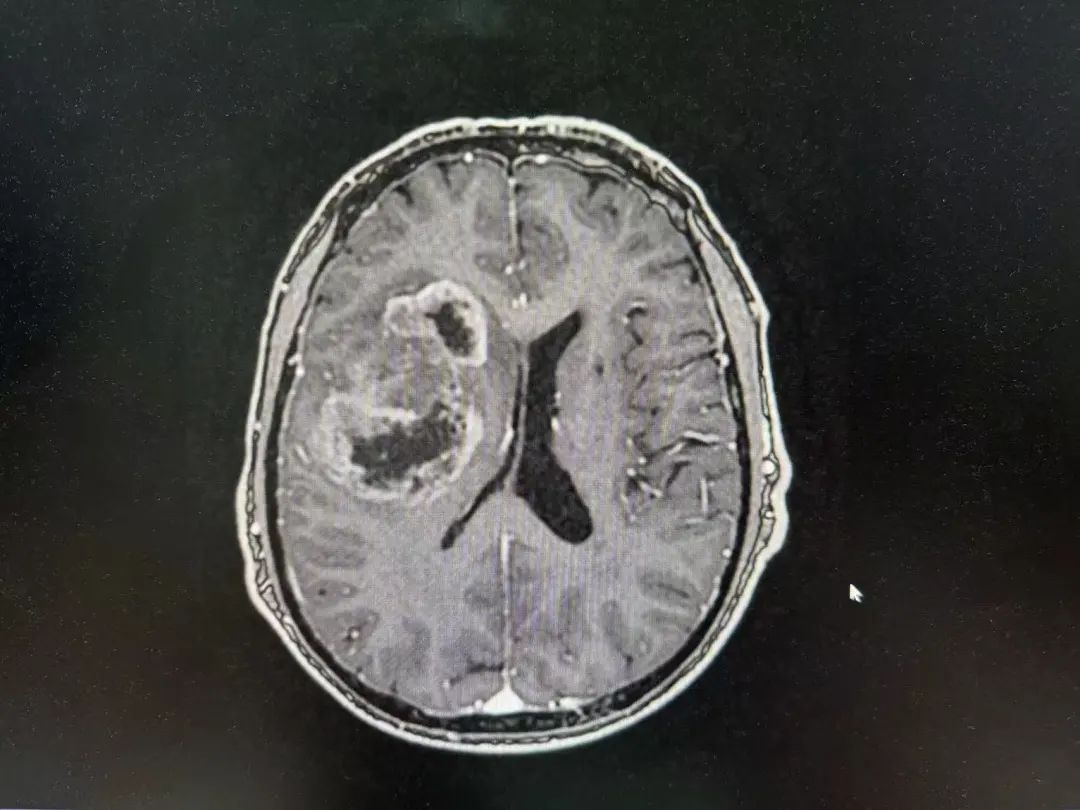

病例特點(diǎn)

男性 | 67歲

主訴:左側(cè)口角流涎10天,左側(cè)肢體無(wú)力7天。

MR:右側(cè)大腦半球腫瘤性病變,考慮高級(jí)別膠質(zhì)瘤(大者大小約3.8cmx4.6cmx3.4cm)。